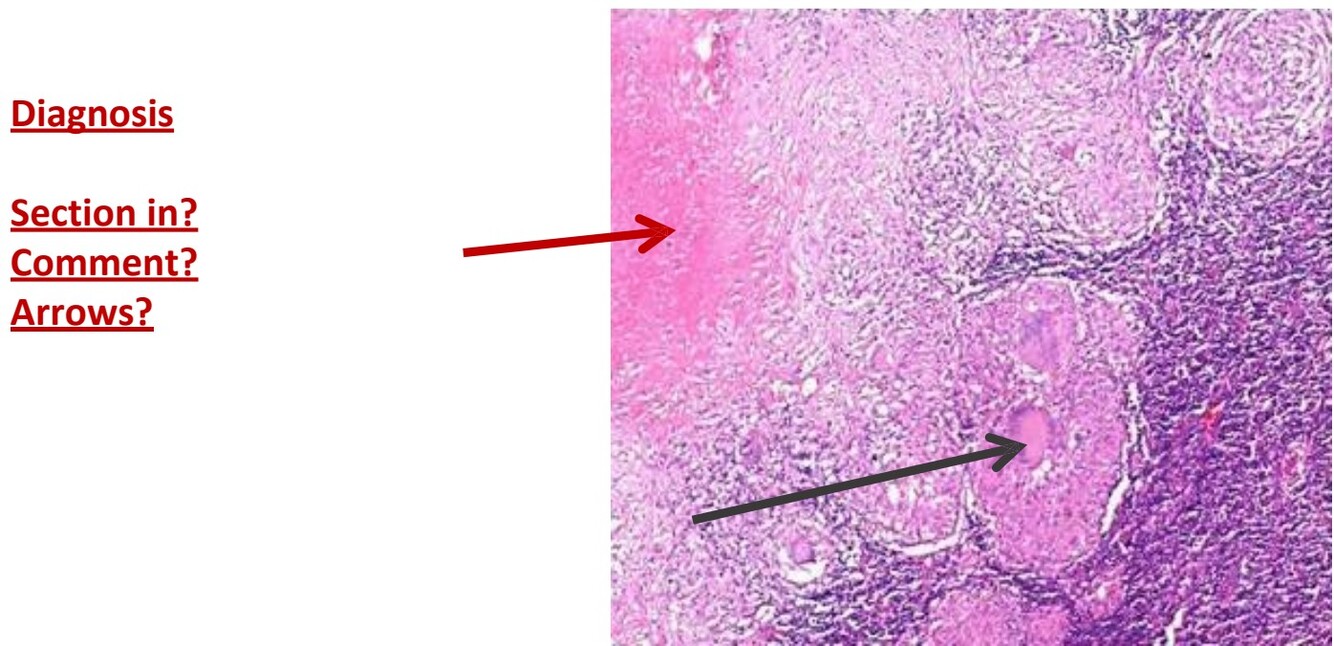

Metastatic carcinoma, lymph nodes

In lymph nodes

Partial replacement of nodal tissue by malignant tumor deposits

Tumor is solid in masses

Arrow points to tumor emboli.